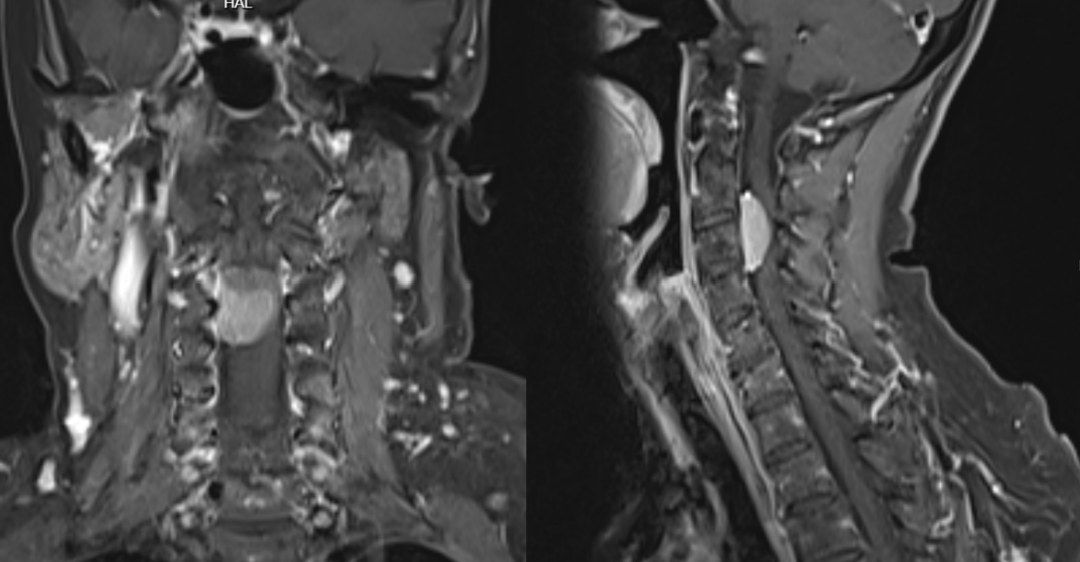

入院查脊髓MRI提示颈2-3椎管内占位,考虑为颈2-3椎管内脊膜瘤,完善相关检查后行颈椎管内肿瘤切除术。

术前磁共振图片:

术后磁共振:肿瘤完整切除